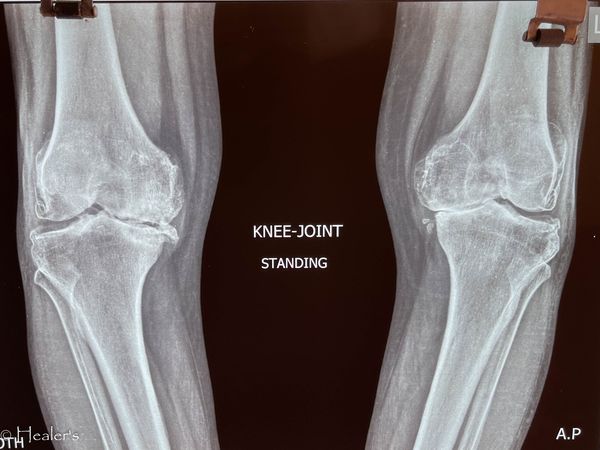

total knee replacement of 58 year old woman

This is one of my early IPGMER days total knee replacement (tkr) surgery done on the right knee for grade 4 osteoarthrosis with medial tibial deficiency that was counteracted with bone graft held with screws. This post would be incomplete without gratitude to Dr. Debasis Mukherjee and Dr. @Chetan Chetan